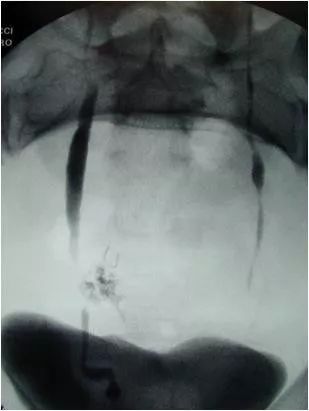

图2 术中静脉肾盂造影与逆行肾盂造影联合影像。子宫切除术造成的双重损害——右侧输尿管横断合并外渗,左侧输尿管结扎